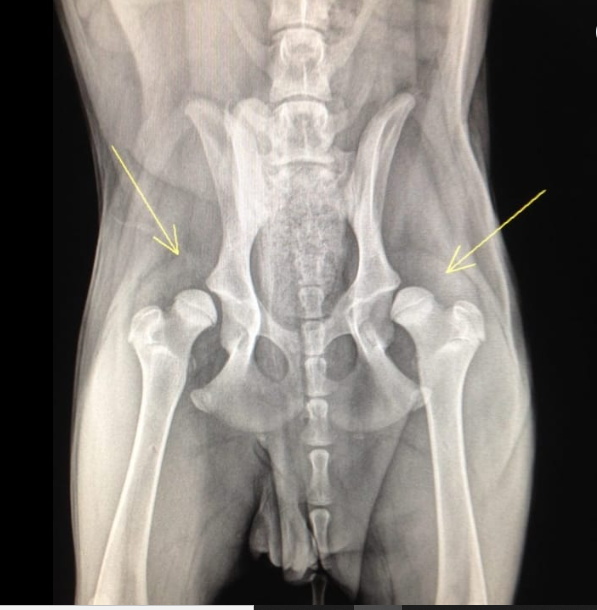

Dysplasie Hanches et Coudes

"Depister la dysplasie du chiot Vous avez adopté un adorable chiot, mais il est de race prédisposée à la dysplasie des hanches…...